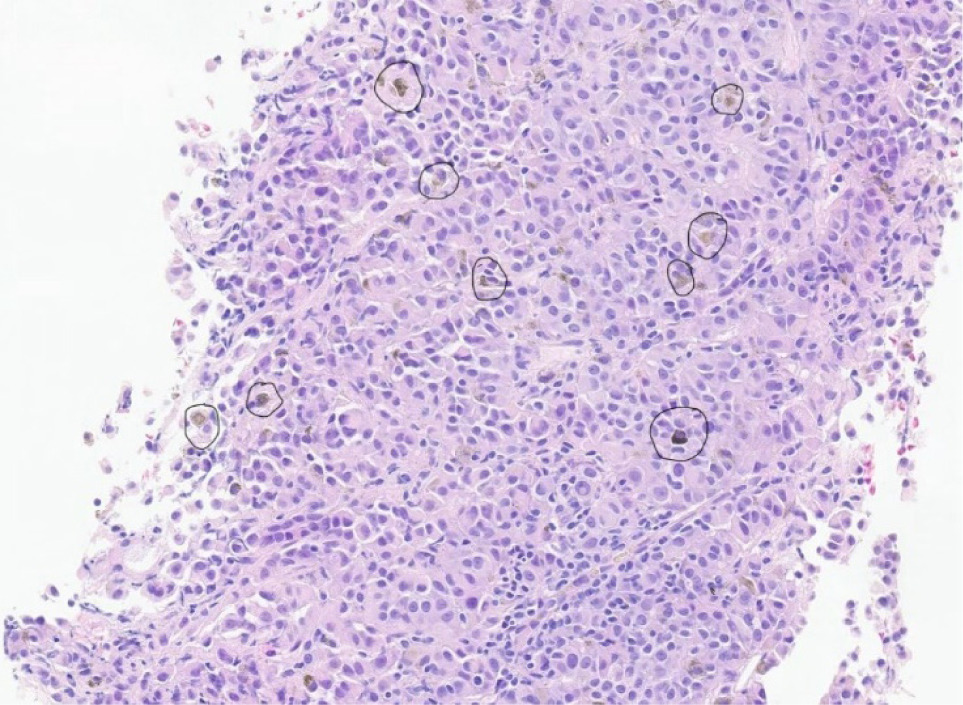

Figure 2: This is a histopathological image of the metastatic melanoma showing pigmented, atypical cells with abundant melanin (in dark circles). The tumor cells appear brown to black against the background of eosinophilic (pink-purple) H and E stain.